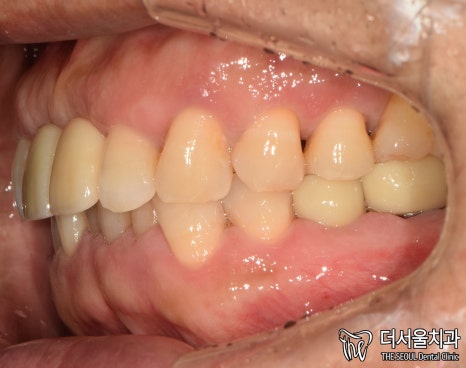

5. 완료

현충일 공휴일 정상진료

최종 완료된 모습입니다.

첫 진료 때보다 깔끔해졌죠?

치아와 비슷한 색으로 된

‘지르코니아’ 크라운을 씌워드렸는데요.

튼튼하다는 특징도 있어

많은 분께 선호되고 있는 재료입니다.

실제로 보면 이렇게

다른 치아와 크게 다르다는 점이 없죠?

환자분도 치료 결과에 만족스러워 하셨습니다.

엑스레이로 한번 더 체크했을 때도

뼈와 잘 붙었습니다.